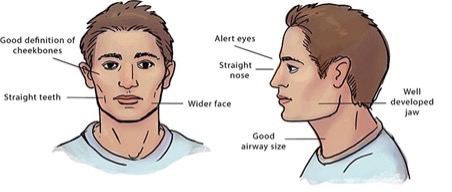

Myofunctional therapy is a program of specific exercises that target the facial muscles. The exercised-based therapy focuses on the mouth, tongue, and face muscles. These exercises are designed to develop, improve, and promote proper breathing, chewing, and swallowing. These exercises do strengthen the tongue. Below are frontal and side views of good normal growth and development of the orofacial structures.

Delayed Neuromotor Development: The abnormalities found in the orofacial muscles and structural differences can lend to some problems. This can be seen with the slow growth of the cheekbones and jaw.

Obstructive Airway: this could be from expanded tonsils, a deviated septum, or allergies. These issues effect the flow of air through the nasal airway. In turn, this can cause the jaw to change to an improper position causing adaptation to mouth-breathing since the nasal airway is obstructed.